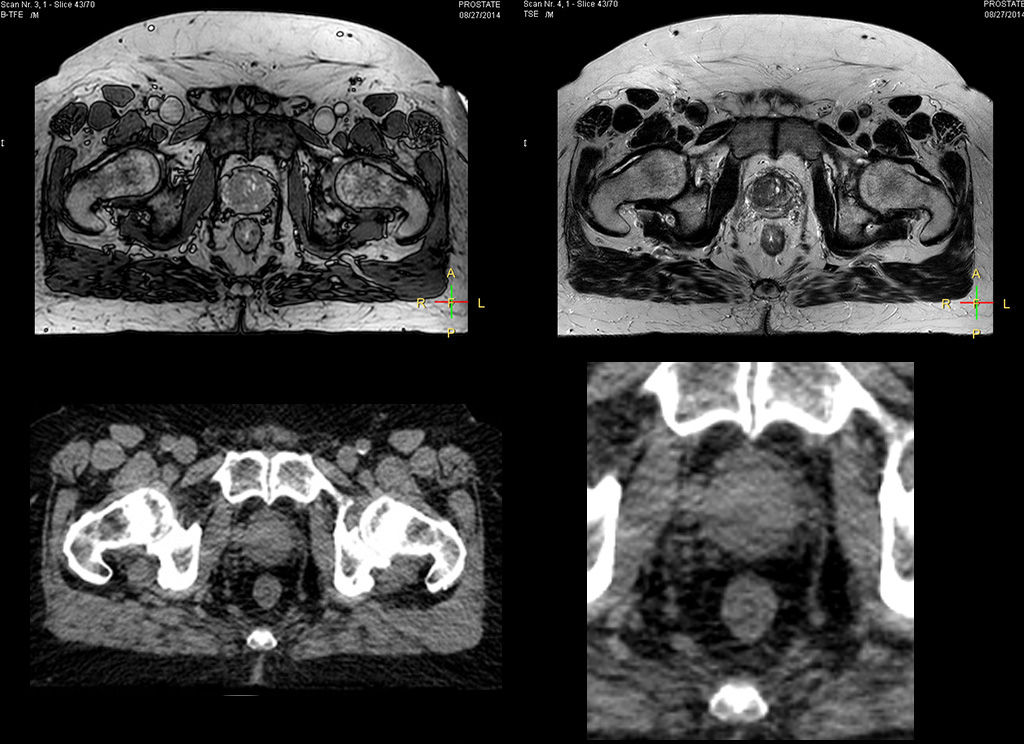

“The biggest problem for CT-based planning, especially in prostate, is you can’t see the cancer very well,” says Dr. Stevens. “On CT it can be quite challenging to see the edge of the prostate especially at the apex. When the edge of the prostate can’t be delineated well on CT, radiation oncologists will increase their margins a little bit so they don’t miss it, but that can also increase toxicity.” “Using MR, the prostate is well delineated. We quickly see the edges of cancerous tumors like in prostate cancer, and as normal structures can be defined, we can optimize the treatment plan to protect these organs and their normal function. This can potentially improve the outcome. And it improves workflow as well. We can contour more quickly, confident that the tumor is going to be in the field.” “The Ingenia 3.0T MR scanner provides high resolution allowing us to make scans fast for the patients. It also gives the potential to include methods like MR spectroscopy and diffusion weighted Imaging, which we’re in the process of doing right now,” Dr. Stevens adds.

“When a patient registers, first CT simulation and MR simulation are done, followed by CT-MR registration on Pinnacle3. Then the target and normal organ delineation is performed on MR images. Meanwhile we create a reference CT image for online treatment and localization correction. During the treatment phase we can perform additional MRI scans to visualize the anatomy changes and create an adaptive plan. This plan basically adapts the treatment plan to the changes.” “Along with its great benefits, MR has introduced some new challenges,” Dr. Stevens says. “Radiation therapy teams generally have no experience with MR. The Philips training helped us to implement fully the things we can do with the Ingenia MR-RT system. So the training, as well as having a good MR physicist, is critical.”